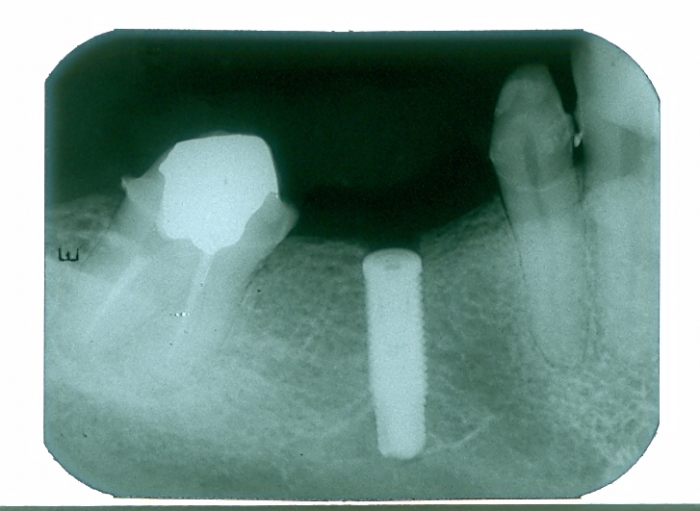

Raio X do implante